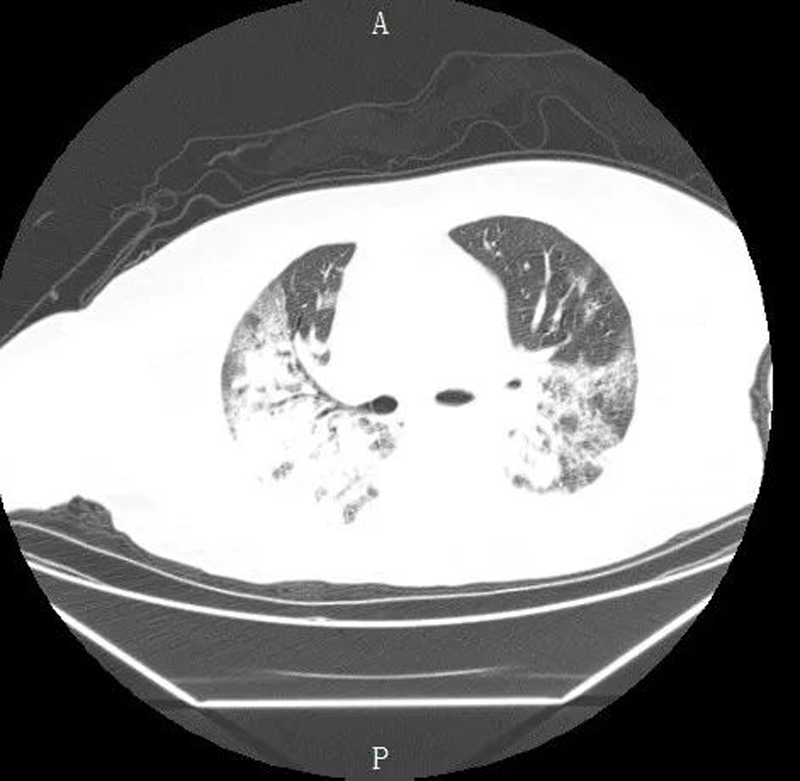

去年12月,身患高血压的童阿姨因反复咳嗽咳痰、呼吸困难5天,输液治疗未见好转来到我院治疗,入住呼吸与危重症医学科。检查结果为新冠病毒核酸阳性,胸部CT显示存在严重肺部感染(俗称“大白肺”),病情极其危重。

入院检查时存在严重肺部感染

经过呼吸内科与重症医学科、ICU的共同努力,童阿姨终于转危为安,病情稳定后,转入呼吸内科与重症医学科继续巩固治疗,此时复查肺部CT显示白色感染明显吸收。